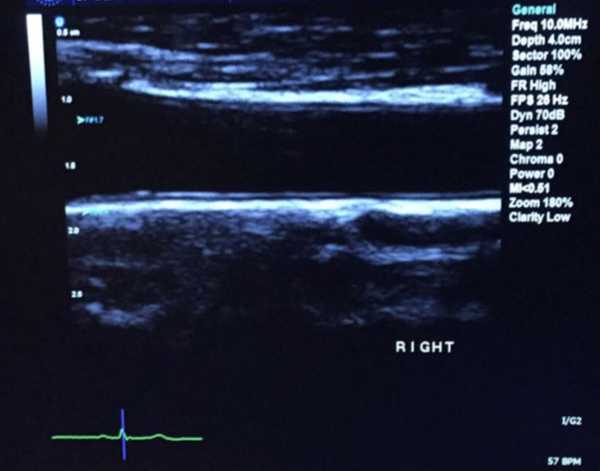

Екран ультразвукового дослідження, що показує 2D-зображення сегмента загальної сонної артерії. Центральна чорна область – це канал усередині сонної кровоносної судини, а більш чіткі шари з кожного боку цього центрального каналу – це стінки артерії. На периферії зображення показано м’які тканини, що оточують артерію.

Спочатку дослідники провели ультразвукове дослідження сонних артерій 135 людей з тяжким пародонтитом, щоб встановити базовий рівень товщини. Вони також виміряли, наскільки розширювалися артерії при збільшенні кровотоку — показник функціонування кровоносних судин — і взяли зразки крові, щоб точно визначити маркери запального та оксидативного стресу. Усі особи були здоровими, окрім захворювань ясен.